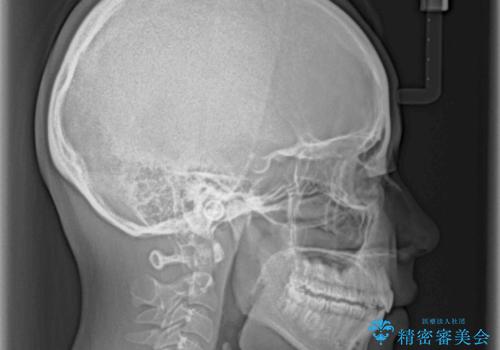

口が閉じられない 抜歯矯正で口元をスッキリと

- 上下の出っ歯を気にして来院された患者様です。

口元を積極的に引っ込めるために、上下左右の第一小臼歯を4本抜歯することとしました。

しっかりと通院するようになってからは順調に治療が進み、横顔の印象が変わるほどスッキリとした口元となりました。